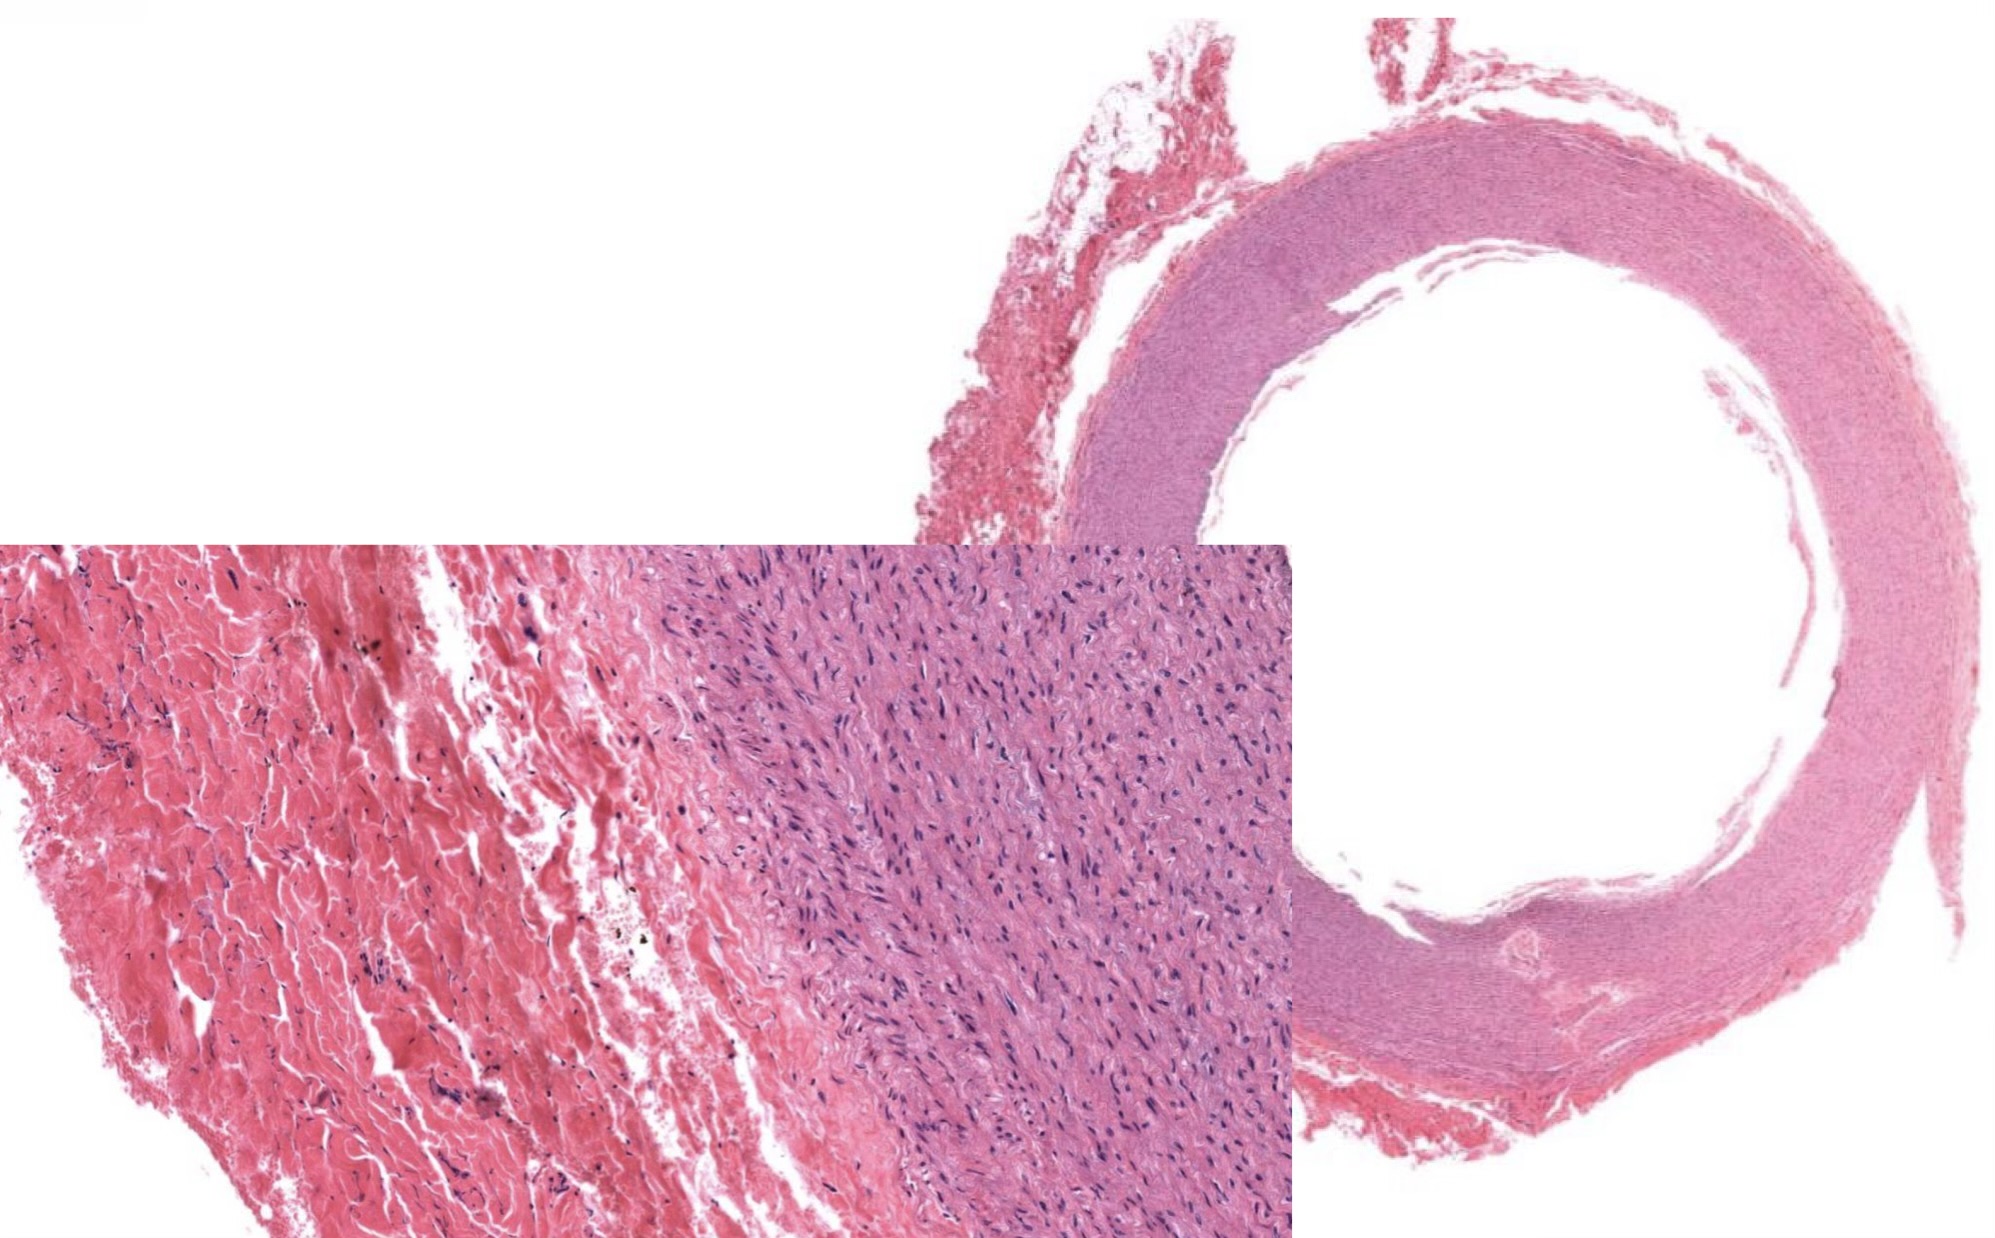

Idenitfy the Vessel and what are the Properties?

Large/Elastic Artery

close to heart

Ti made of endot + elastin + collagen

Tm made of elastic F + collagen; Smooth M!

Te made of DICT w/ vasa vasorum

Identify the Vessel and the Layer pictured

Large/Elastic Artery Ti

Large/Elastic Artery Tm!

Large/Elastic Artery Ta

Large/Elastic Artery Ti, Tm!, and Ta